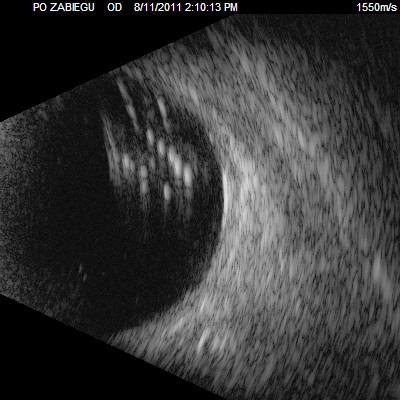

Dziwne mętów

Przedstawiane obrazy ultrasonograficzne® są oryginalne i pochodzą z mojej praktyki lekarskiej